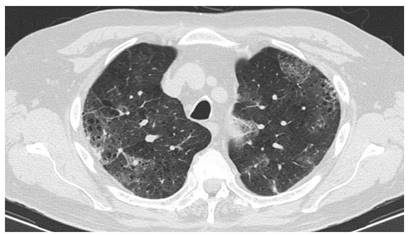

Se vuelve a interrogar al paciente, el cual refiere inicio reciente de montelukast (dos semanas previas), por episodios recurrentes de broncoespasmo considerándose posible asma superpuesta a EPOC. Se suspende manejo con inhibidor de leucotrieno y se indican pulsos de glucocorticoides por tres días con mejoría significativa de la sintomatología. Al descartar como causas, las patologías autoinmunes e infecciosas sin presentar manifestaciones asociadas a ninguna de estas entidades e inicio reciente de un medicamento con cambios agudos en la tomografía de tórax con respecto a la previa (Figura 1 y 2) y hallazgos de hemorragia alveolar difusa, se considera alta probabilidad que haya cursado con una reacción adversa al montelukast. No se realizó TACAR de control dada la mejoría clínica presentada por el paciente.

Figura 2 Tomografía simple de tórax, ventana pulmón con corte axial dos semanas posterior al inicio de montelukast. Deterioro de la transparencia de ambos parénquimas pulmonares a predominio de lóbulos superiores con áreas de distribución no segmentaria con patrón de «vidrio esmerilado» de etiología inespecífica y cambios por enfisema centrolobulillar.